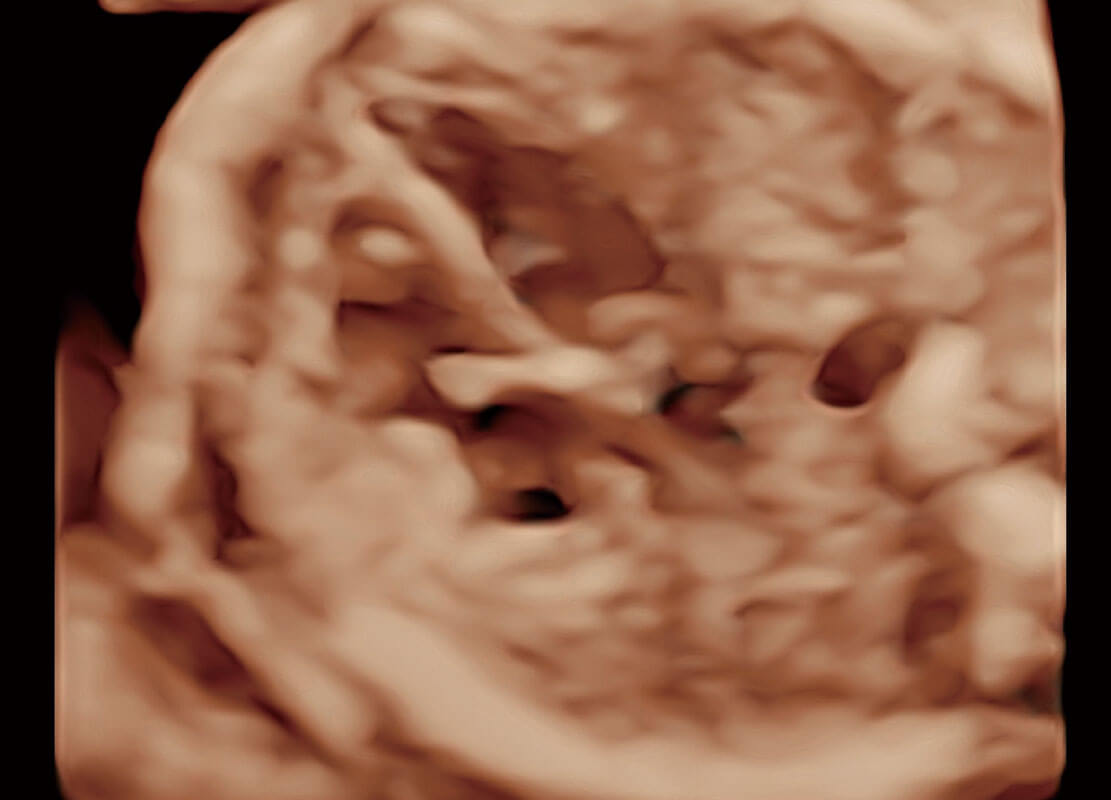

腔内三维-光影成像

光影成像-孕囊